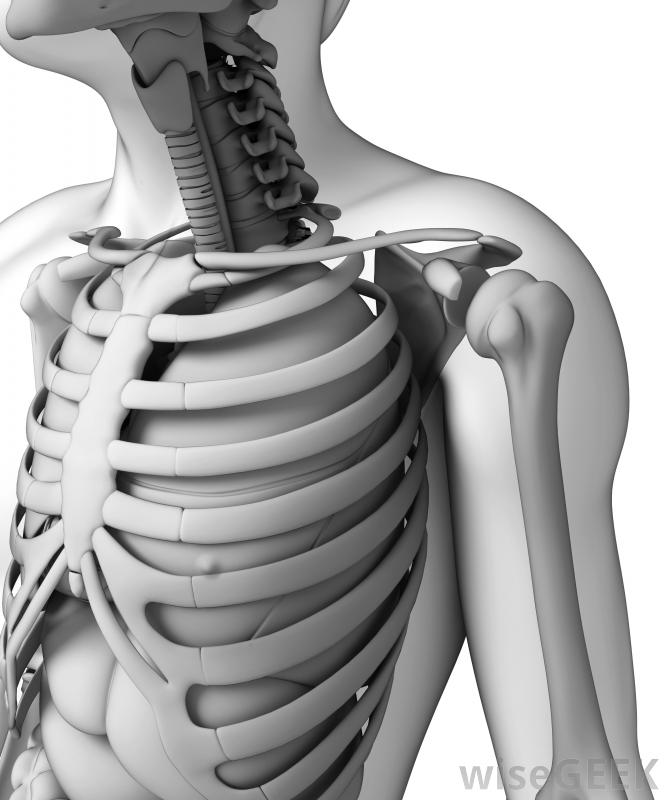

胸廓也被称为胸腔。它由12对肋骨组成,通过12根椎骨连接到身体后部,胸椎是脊椎的一部分,位于颈椎或颈部的正下方。保护心脏、肺等重要器官,肝脏和胃是胸腔的一个非常重要的功能上部10对肋骨连接在身体前部,或前部。由于上部的7对肋骨围绕侧面朝前弯曲,每根肋骨都会遇到一块薄薄的软骨,这是一种非常坚韧但柔韧的组织。软骨延伸到它与胸骨相连的地方,通常称为胸骨

胸腔包括12对肋骨,胸骨和12个椎骨。第八、第九和第十对也环绕在身体前部,但是连接到胸骨的软骨是共享的,而不是单独的一块,第11对和第12对肋骨没有前部附着物,这就是它们通常被称为"浮动"肋骨的原因胸前胸腔的插图和X光片可能只显示第11对肋骨的一部分,而第12对肋骨往往很短,除了从身体的侧面或背面看,它根本看不出来。

手术时有时需要切开胸骨才能进入胸腔。肋骨与胸骨相连的肋软骨阻止了整个胸腔的形成骨骼。这一点很重要,因为呼吸依赖于胸腔的扩张和收缩,而骨骼太硬,无法满足胸腔内呼吸所需的灵活性。胸腔的形状被称为笼子,因为它包围了身体的大部分躯干和肋骨对制作类似于笼子的钢筋外观。